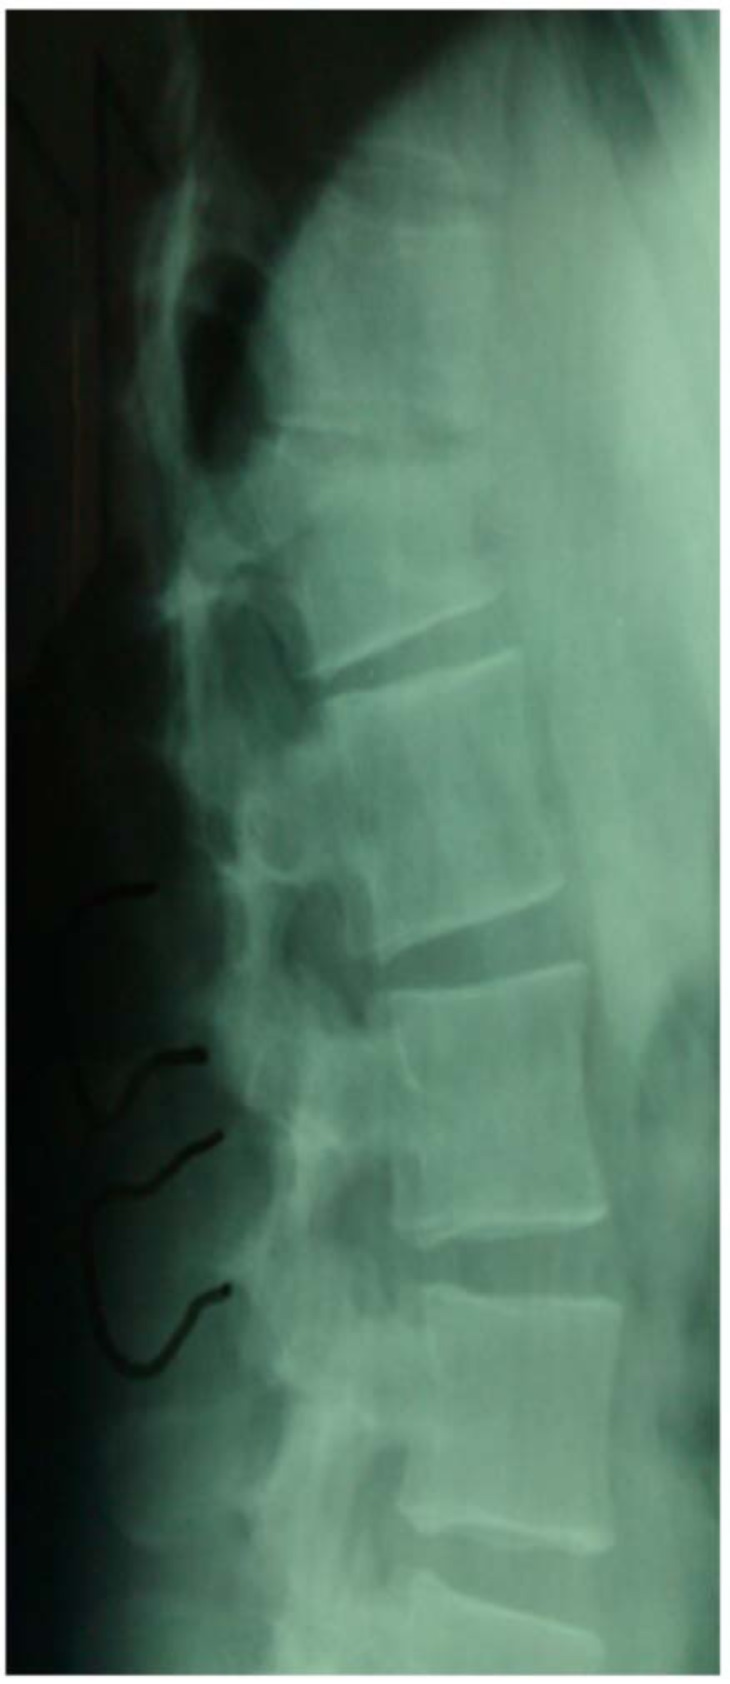

Upon admission, palpation revealed tenderness at the thoracolumbar region. His neurologic examination was normal with no motor or sensory deficit of the lower and upper limbs. Ultrasonography was performed to exclude blunt abdominal concomitant injuries. Simple radiographic evaluation of the cervical spine, thorax and pelvis did not demonstrate associated injuries. Radiographs (Figs. 1, 2) and CT scans (Fig. 3) of the thoracolumbar spine revealed a transverse fracture at the level of T12. The CT scan further demonstrated a split of the posterior elements, progressing anteriorly into the vertebral body. Conservative treatment was decided and the patient, following an initial period of bed rest, was mobilized wearing a thoracolumbar orthosis. Appropriate antithrombotic prophylaxis with low molecular weight heparin was administered, until full ambulation was achieved. The patient was followed up with serial thoracolumbar radiographs for the first 6 weeks of ambulation and later on, in one month intervals. The thoracolumbar orthosis was applied for three months. At the 5th month follow-up, he was pain free with radiographic signs of mild vertebral kyphosis. Upon completion of treatment, he returned successfully to pre-injury levels of daily activity, without any impairment.

Fig. (1). Lateral radiograph demonstrating a T12 transverse fracture.